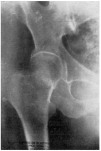

Fracaso número 3(observación número 7). Carmen J., sesenta años. A los cincuenta y tres días de presentar una fractura transcervical del cuello del fémur intentamos el enclavijamiento, que no pudimos realizar por no funcionar los rayos X a causa de una avería eléctrica. No pudimos repetir la intervención hasta pasados veinticuatro días, resultándonos entonces imposible reducir correctamente la fractura (fig. 5., A y B). Enclavijamiento (fig. 5. C) técnicamente defectuoso. A los cuatro meses a causa de presentar una supuración en la herida ingresa nuevamente en el servicio. Una radiografía practicada la misma tarde demuestra la ascensión del clavo, el cual está a punto de perforar el borde superior de la cabeza. Un mes después se extrae dicho clavo. La radiografía parece demostrar una ausencia de consolidación. La enferma deambulaba relativamente bien con ayuda de un bastón.

Figura 5. A: obs. núm. 7. En esta proyección la reducción es, aparentemente, buena; sin embargo, la zona clara que existe a nivel de la línea de fractura, demuestra la ausencia de reducción. B: obs. núm. 7. La fractura no está reducida. C: observación núm. 7. El clavo ha sido colocado de-masiado cranealmente.

La causa fundamental del fracaso en esta observación reside en no haber reducido correctamente la fractura, cosa que hubiéramos conseguido con toda probabilidad gracias a una tracción continua mediante un Kirschner colocado en la metáfisis femoral inferior.